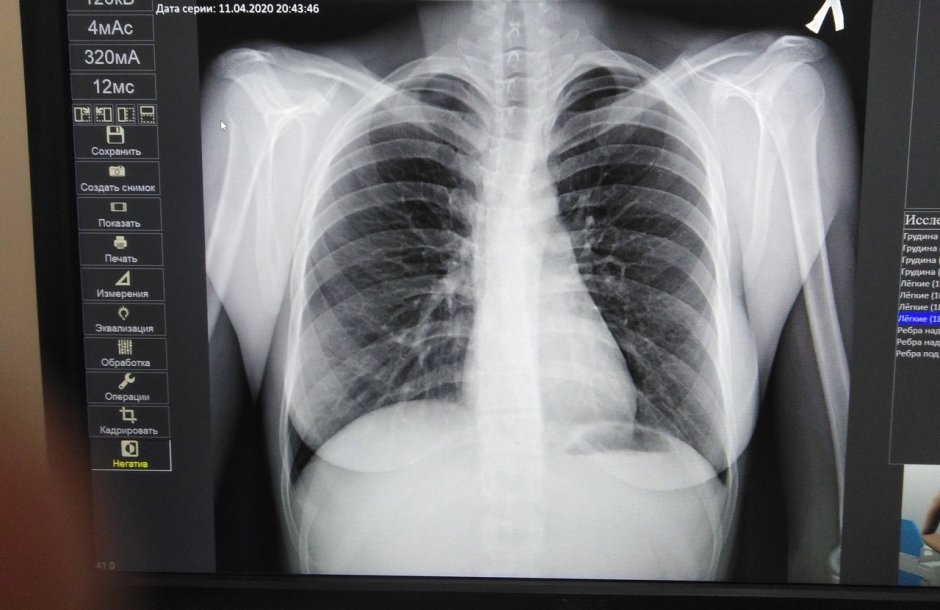

8. Под рентгеном

10. Рентгеновские снимки человека

13. Скелет рентген

34. Рентген человека

61. Рентген снимок